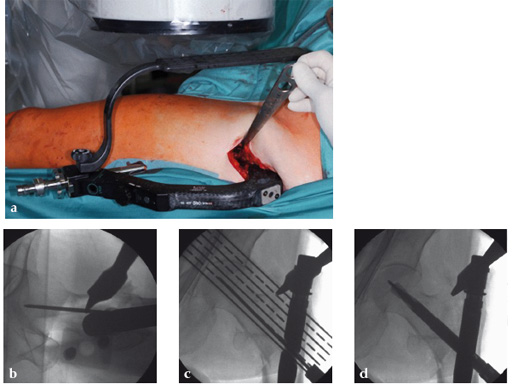

Use of the guide-wire aiming device in an 87-year-old woman.

a Clinical picture of the whole aiming and insertion construct.

b After closed and minimally invasive open reduction with a Hohmann retractor pushing on the anterior aspect of the femoral neck for better axial alignment, the guide-wire aiming device has been mounted to the aiming arm and helps to identify the optimal position of the guide wire in the femoral head.

c The K-wire runs parallel to the chosen line of the aiming device. In AP projection the tip of the blade should be positioned in the center of the femoral head.

d In AP projection the tip of the blade should be positioned in the center of the femoral head, in lateral projection the blade should run parallel to and in middle of the neck and also end dead center of the femoral head. The distance of the tip of the blade to the joint should be approximately 10 mm. No predrilling is recommended in osteoporotic bone.